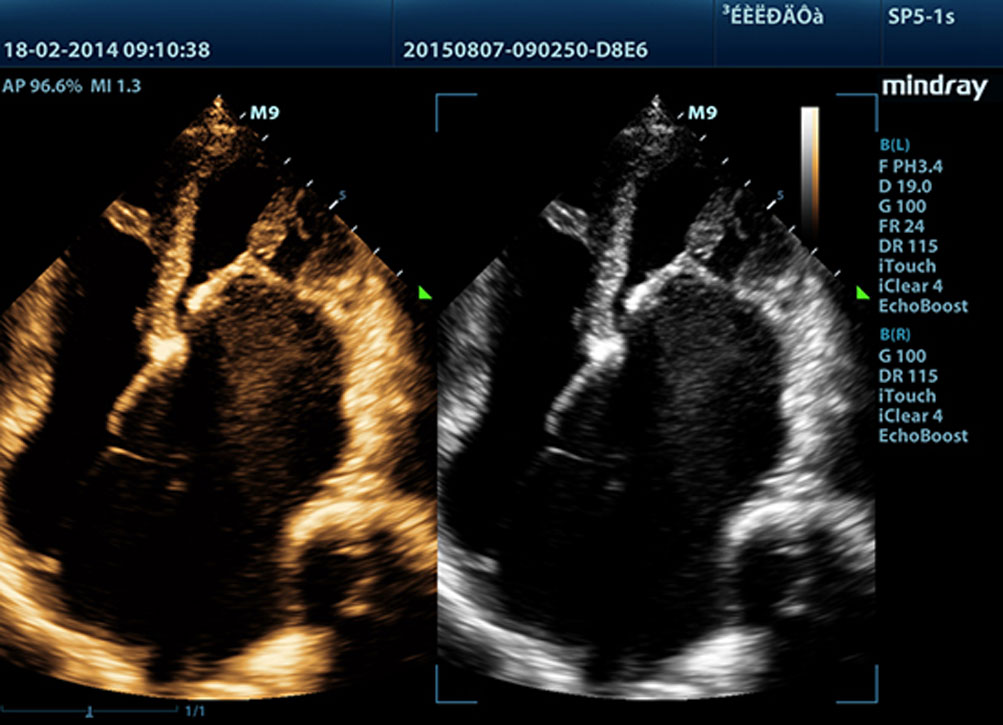

Echo Boost?

Mindrays einzigartige adaptive Signalverarbeitung mit intelligenter Echoerkennung, die zwecks Nutzung der nat├╝rlichen Signal-zu-Rauschen-Information zur Verst?rkung der schwachen Echosignale bei gleichzeitiger Unterdr├╝ckung der diversen Umgebungsger?usche entwickelt wurde, liefert eine ausgeglichenere Brillanz der Bilder und eine verbesserte Visualisierung der Gewebsschichten des Myokards.